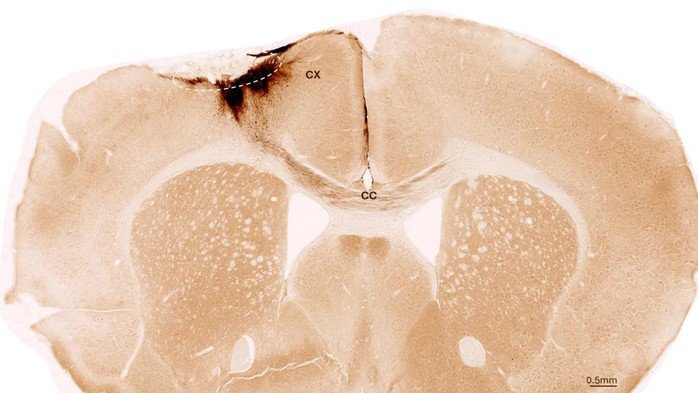

Thí nghiệm của các nhà khoa học Mỹ và Thụy Sĩ đã vạch ra con đường mới để phát triển các phương pháp ...